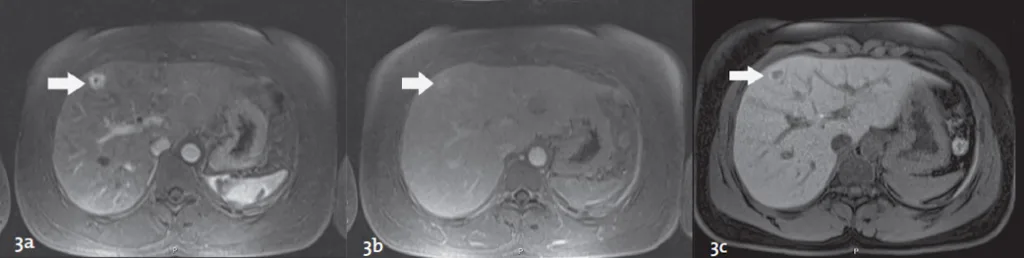

Figure 2. Performances de la séquence de diffusion pour la détection des lésions secondaires. Après injection de chélates de gadolinium, une seule lésion de 8 mm du segment 5 est visible en phase portale (flèche figure 2a). Sur la séquence de diffusion (Pondération diffusion b = 800 sec/mm2), plusieurs lésions secondaires additionnelles sont nettement identifiables (têtes de flèche figure 2b) en plus de la lésion du segment 5 (flèche figure 2b).